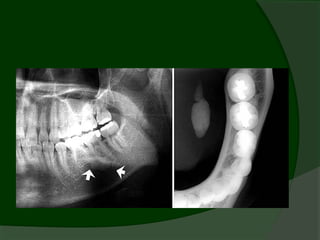

Diagnostics: Plain occlusal film

   Effective for

intraductal stones,

while….

   intraglandular,

radiolucent or

small stones may

be missed.

80-90% of SMG calculi are radio-

opaque

50-80% of parotid calculi are radiolucent

   30% of SMG stones are multiple